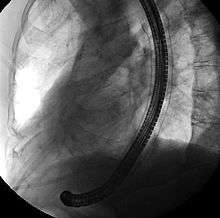

Self-expandable metallic stents are typically inserted at the time of endoscopy, usually with assistance with fluoroscopy or x-ray images taken to guide placement. Prior to the development of SEMS small enough to pass through the channel of the endoscopy, SEMS were deployed using fluoroscopy alone.[13]

Esophageal SEMS are placed after a gastroscopy is performed to identify the area of narrowing. The area may need to be dilated in order to allow the gastroscope to pass.[14] The tumour is usually better seen with the direct vision of endoscopy than on a fluoroscopic image. As a result, radio-opaque markers are usually placed on the surface of the patient in order to mark the area of narrowing on fluoroscopy. The SEMS is placed through the channel of the endoscope into the esophagus over a guidewire, marked on fluoroscopy, and mechanically deployed (using a device that sits outside of the endoscope) such that it expands when in position. Hypaque or other water-soluble dye may be placed through the passage to ensure patency of the stent on fluoroscopy.[15] Enteric and colonic SEMS are inserted in a similar fashion, but in the duodenum and colon respectively.[16]

Biliary SEMS are used to palliatively treat tumours of the pancreas or bile duct that obstruct the common bile duct. They are inserted at the time of ERCP, a procedure that uses endoscopy and fluoroscopy to access the common bile duct. The bile duct is cannulated with the assistance of a guidewire and the sphincter of Oddi that is located at its base is typically cut. A wire is kept in the bile duct, and the SEMS is deployed over the wire in a similar fashion as esophageal stents. The location of the SEMS is confirmed by fluoroscopy.[17]